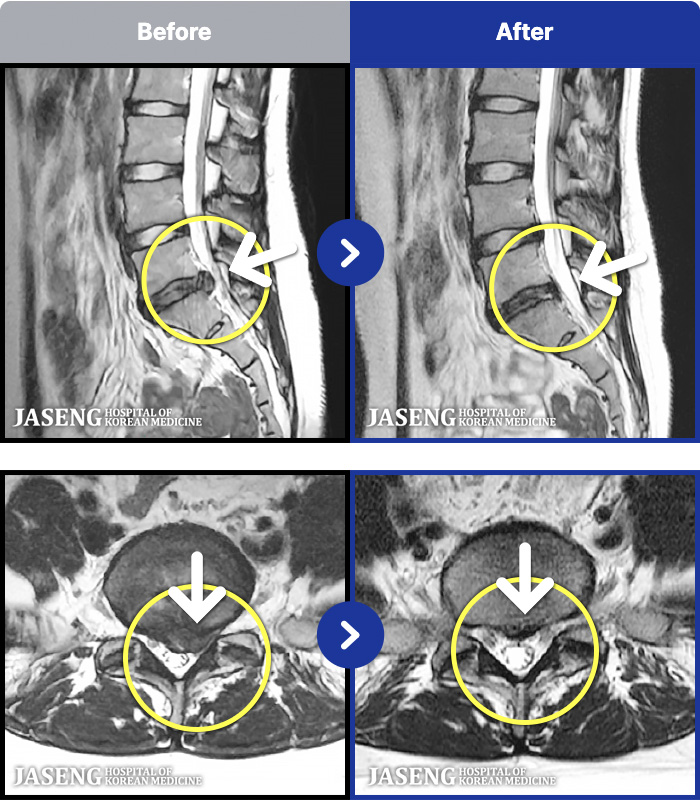

MRI ġ

MRI ũ ʸ Ȯϼ.